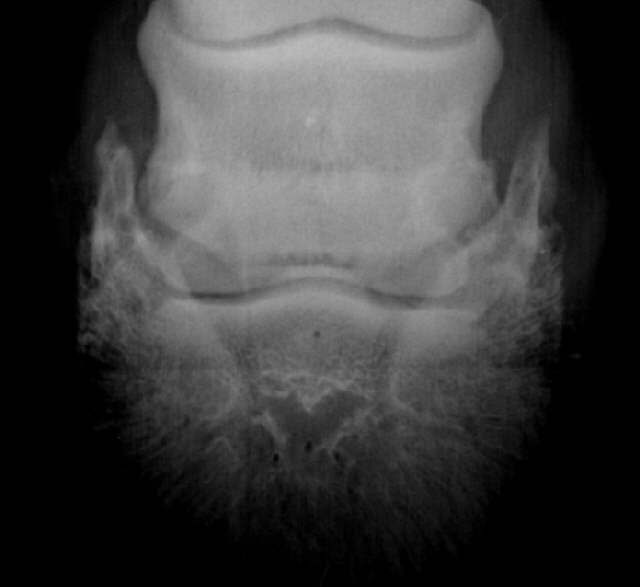

Oseolytische Defekte

Sklerosierung und deutliche Zubildungen am unteren Rand des Strahlbeines. Röntgenklasse IV